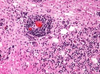

What are common organism in septic emboli in the CNS?

- Cattle – Actinomyces/Trueperella pyogenes, Haemophilus somni, Staph aureus

- Lambs – staph aureus (tick pyemia)

- Horse- strep equi

- Dog- staph aureus